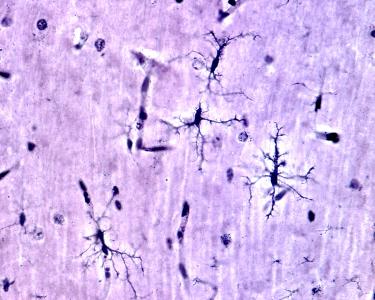

La microglie, un support structurel à l'intégrité neuronale

Exploiter cette fonction possible et naturelle de la microglie pourrait constituer une nouvelle approche thérapeutique prometteuse dans l’épilepsie : ici, les chercheurs observent, chez la souris modèle de crises, que plutôt que de simplement nettoyer les débris cellulaires, la microglie commence à former des poches qui n’engloutissent pas le matériel endommagé, comme le font de nombreuses cellules immunitaires mais « regonflent » les dendrites, les branches des cellules nerveuses qui transmettent l'influx nerveux. En résumé, écrivent les scientifiques, la microglie semble favoriser leur guérison.

Ces petits sacs à processus microglial perdurent pendant des heures, rétrécissent de temps à autre, et semblent redonner aux dendrites une structure et une fonction normales.